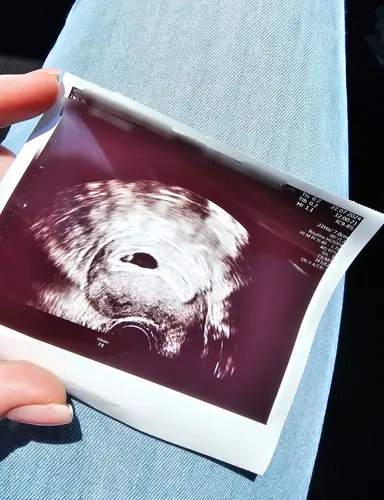

Mein Termin von Freitag letzter Woche wurde auf heute geschoben. Wir sind so glücklich. Haben den Herzschlag gesehen und die SSW passt zur Größe 🥰